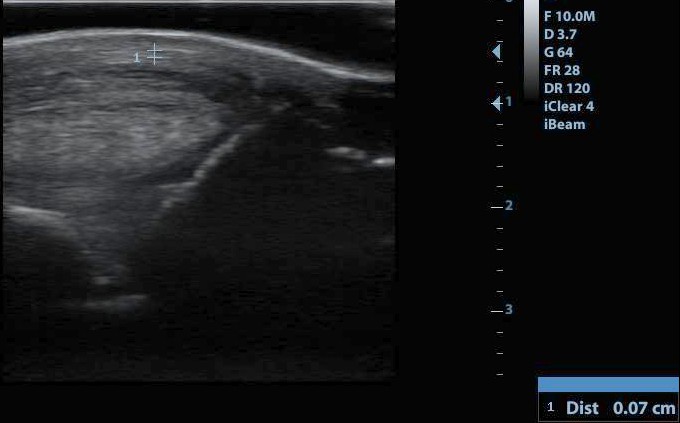

A csüd mögött helyeződő gyűrűszalag mérése (normális méretű szalag)